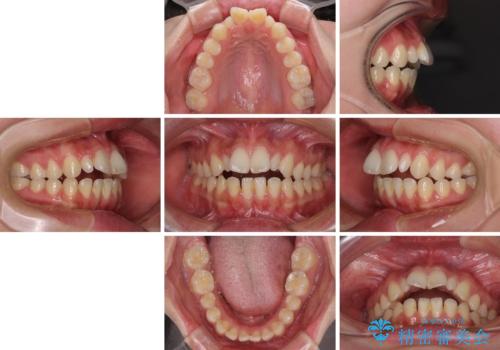

- 前方に飛び出した前歯を気にして来院された患者様です。

遠方の地元へ転居する予定があるとのことで、インビザラインによる治療を希望されていらっしゃいました。

上下前歯同士の距離が離れているため、上顎左右第一小臼歯2本を抜歯することで前突を改善することとしました。

しかしながら、左右ともに側切歯が矮小歯であるため、矯正治療で矮小歯前後にスペースを作り、矯正治療後にオールセラミッククラウンにて補綴治療を行うこととしました。